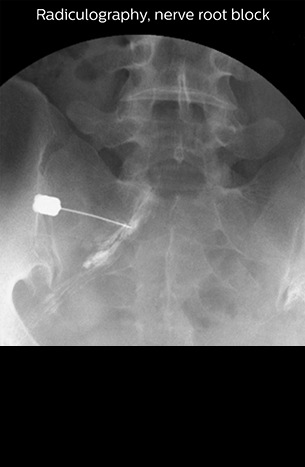

“Before NerveVIEW, diagnosis by MRI alone was sometimes difficult, unless there was a strong suspicion based on clinical symptoms,” says Shoji Yabuki, MD, DMSc, Orthopedic surgeon at Fukushima Medical University School of Medicine. “This is why we routinely perform selective lumbosacral radiculography (nerve root block) and x-ray in such cases. However, radiculography can only depict nerves as far as the contrast agent reaches. When a nerve is distorted by compression, the contrast agent will not pass through this compressed area, preventing us from evaluating the full nerve compression.”

“In such case, we would then browse through axial T2-weighted MR images slice by slice and mentally reconstruct the actual situation based on both radiculography and MRI. Fortunately, NerveVIEW can now very well show nerve courses and presence of nerve compression or edema in one single image series.” “We have often seen NerveVIEW directly depict details of the nerve compression that were not observed by radiculography. Therefore, we think that with NerveVIEW we can reduce the number of invasive examinations, especially for some patients with lumbar plexus symptoms.”